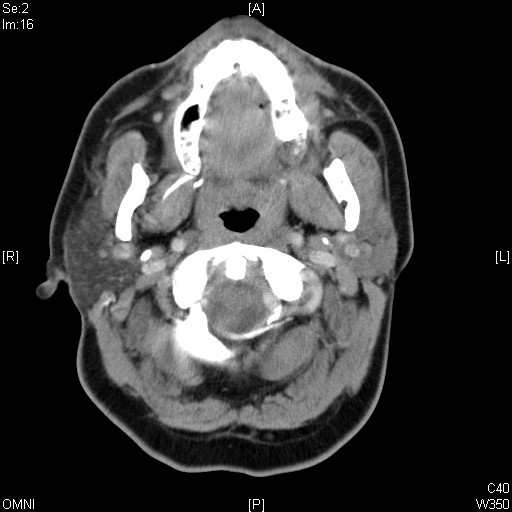

Identify Maxilla and Pharynx